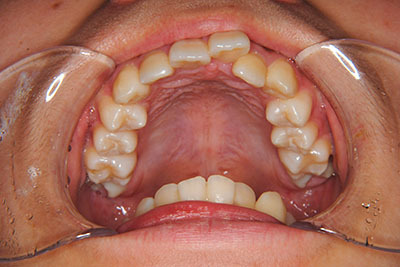

歯が乳歯から永久歯に生え変わった小学生高学年や、中高生でも矯正治療に手遅れということは全くありません。

成長中の顎の骨を矯正できたり、この時期の矯正はおとなになってから矯正治療を始めるよりも短期間で済むことがほとんどです。当院だとおおよそ1年で動的治療(マルチブラケット装置をつける期間)が終わることが多いです。